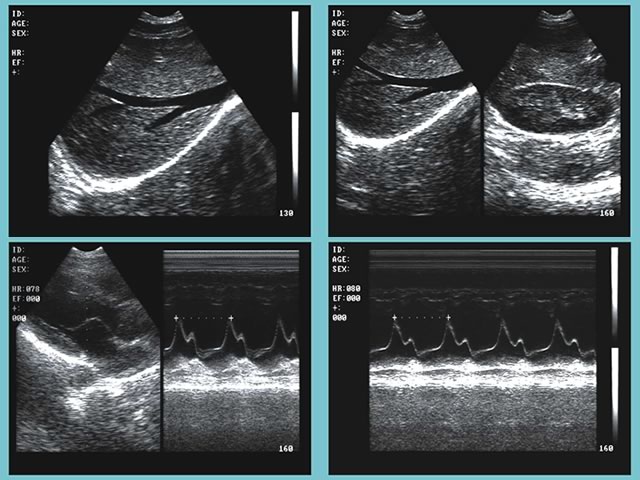

超聲診斷在醫(yī)學臨床上已使用多年。超聲波被廣泛使用,因為其易于使用且價格比其他成像方法便宜。一家大型美國診所在16個房間內(nèi)提供各種各樣的超聲波檢查。 Epiphan VGA Grid有助于超聲檢查人員在空中與相關專家進行溝通

VGA Grid通過VGA圖像采集卡(Epiphan VGA2Ethernet)與安裝在每個檢查室中的最頂尖的超聲波設備相連接。VGA圖像采集卡捕捉來自設備的信號,并通過以太網(wǎng)發(fā)送至VGA Grid。它可以同時捕捉和記錄帶有時間戳的所有會話。進行檢查的超聲醫(yī)師在其得出結(jié)論前,可能需要與專家進行討論。完成成像后,檢查室專家可能有問題需要與主治醫(yī)生、主管或其他受過專業(yè)醫(yī)療成像培訓的專家進行討論。

超聲視頻可以在需要時進行重放或縮小。無論專家們在哪里,他們都能夠查看來自多個來源的視頻。他們通過網(wǎng)絡接口訪問超聲波圖像(錄制或直播)。根據(jù)研究結(jié)果,他們判斷進一步的研究是否會有幫助,然后做報告,并告知病人結(jié)果。 VGA Grid使一次性查看來自多個檢查室的超聲設備信息成為可能,中央控制中心就能監(jiān)測到哪間房間是可用的。高端的設備可以使門診超聲檢查師立即獲得診斷信息,更有效地治療患者。